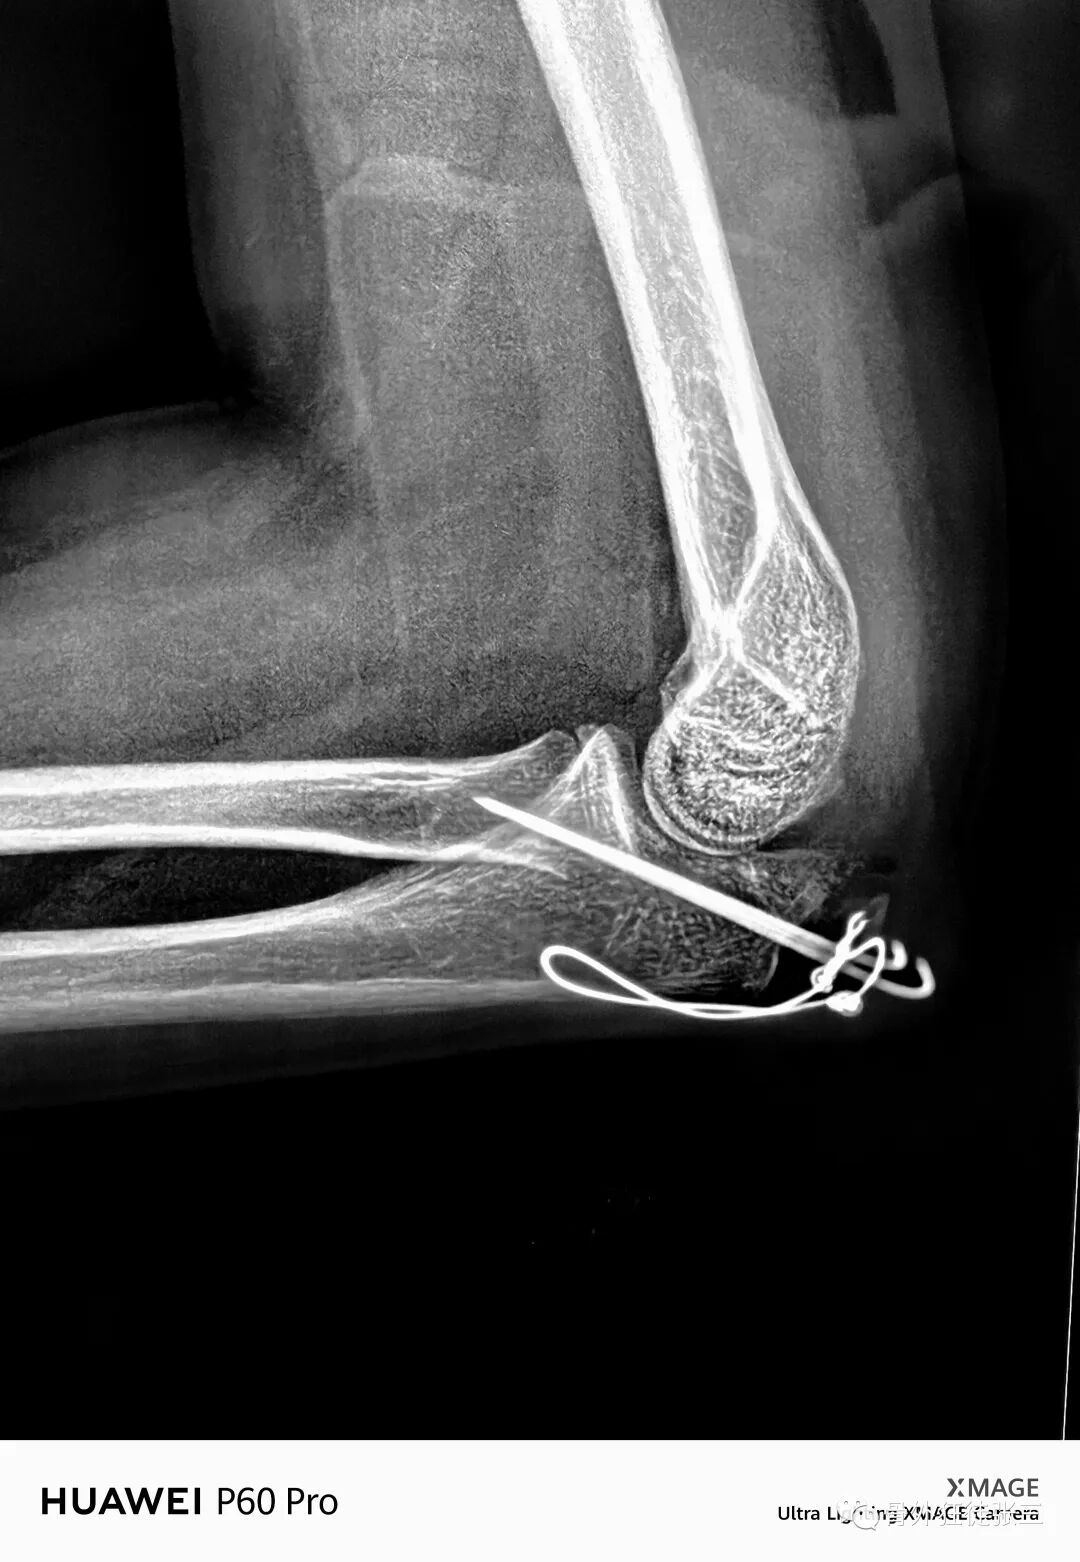

病例14,儿童髁上骨折零切开,桡侧三枚针发散固定